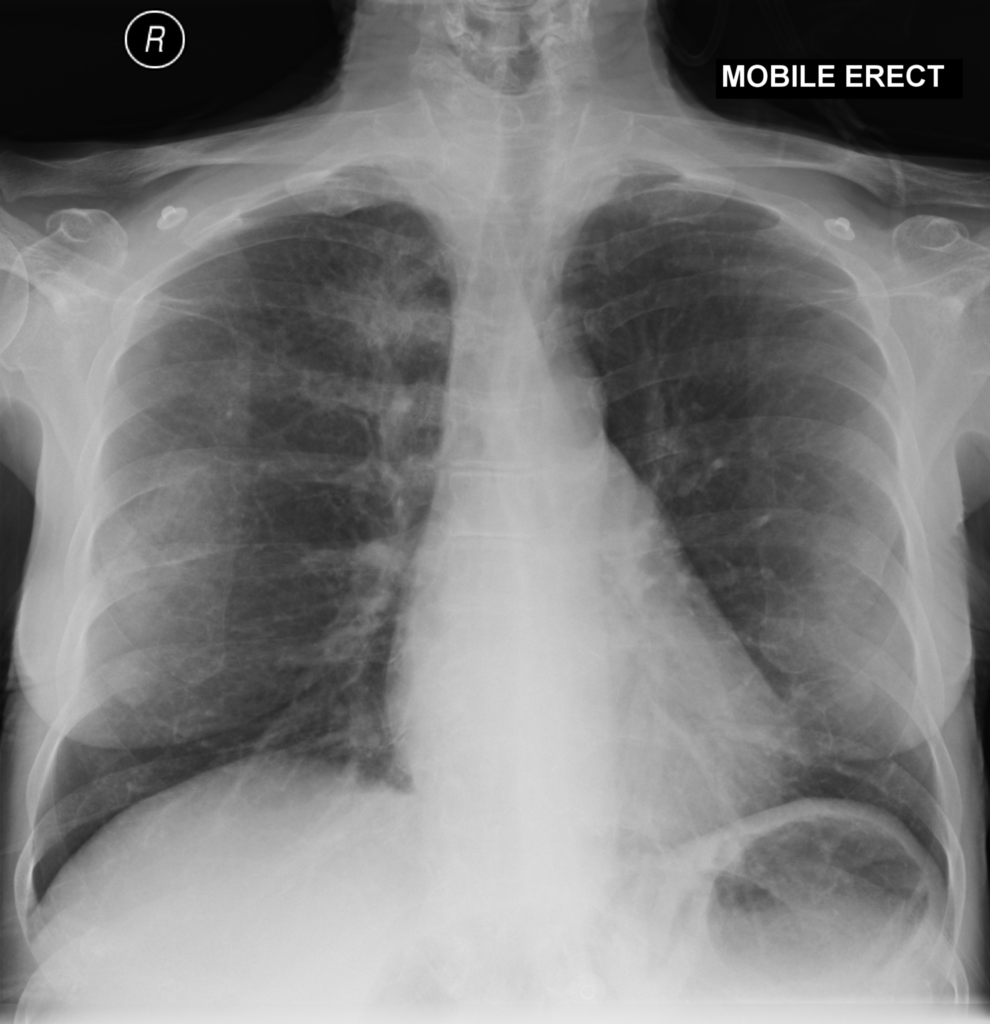

選ぶなら 気道・肺の腫瘍 (呼吸器病New Approach 9) | 飛田 渉 |本 | 通販 医学一般